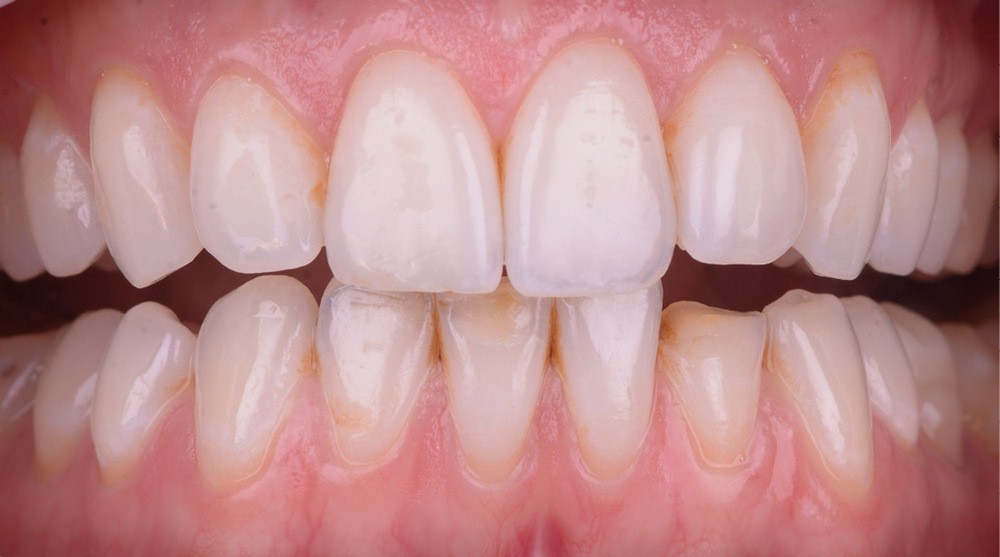

Il existe aujourd’hui sur le marché des résines composites fluides chargées, résistantes mécaniquement et qui présentent de bonnes propriétés optiques. Le choix d’une résine qui présente de bonnes propriétés optiques impose néanmoins une photopolymérisation en fine épaisseur. Ainsi, dans le cas d’une perte de substance supérieure à 2 mm, il est préférable de reconstruire la surface en plusieurs incréments [2]. L’injection de résine au travers de la clé ne concerne ainsi que la couche la plus superficielle.

Afin d’obtenir un comportement optique le plus proche possible de celui de la dent naturelle, l’auteur recommande de réaliser le corps de la dent au préalable à l’aide d’un composite de restauration plus saturé. C’est uniquement la couche la plus superficielle qui est injectée. La technique d’injection de composite nécessite le respect d’un protocole strict et comporte quelques difficultés qu’il convient d’anticiper.